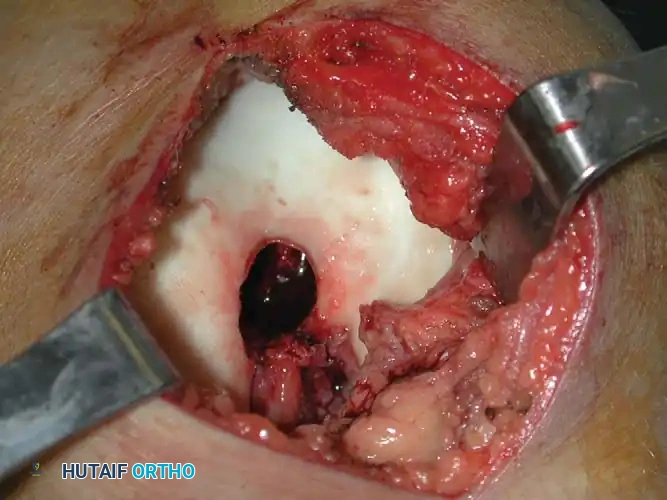

*Fig. 21-6E & F: (Left) Intraoperative photograph demonstrating the large cortical window and the cavity after gross curettage of the intercondylar notch lesion. (Right